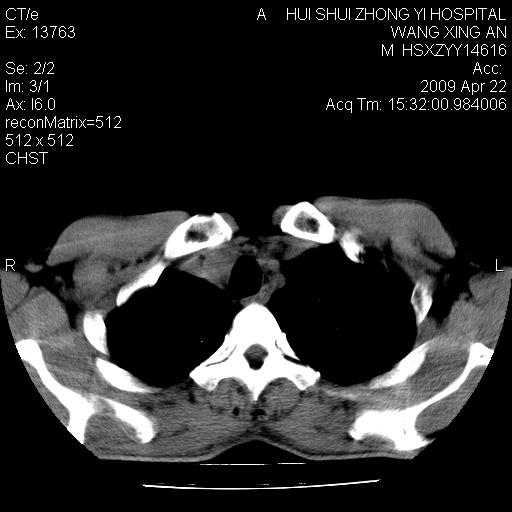

标题: CT19534:患者男、46岁咳嗽、胸痛半月。 [打印本页]

标题: CT19534:患者男、46岁咳嗽、胸痛半月。

1、右下肺中央型肺癌并右肺转移,右肺下叶不张。(右肺有结节影)。

2、右中上肺陈旧性肺结核(因为大多为纤维灶)。

1、右下肺中央型肺癌伴并双肺转移

2、右侧陈旧肺结核

1、右下肺中央型肺癌并右肺转移,右肺下叶不张。(肿块围绕右肺下叶支气管生长,致管腔闭塞右肺下叶不张;右肺有结节影)。

3、右中上肺陈旧性肺结核(右肺见纤维化病灶及点状钙化)。

1、右下肺中央型肺癌并右肺转移,右肺中下叶不张。(右肺有结节影)。胸骨转移